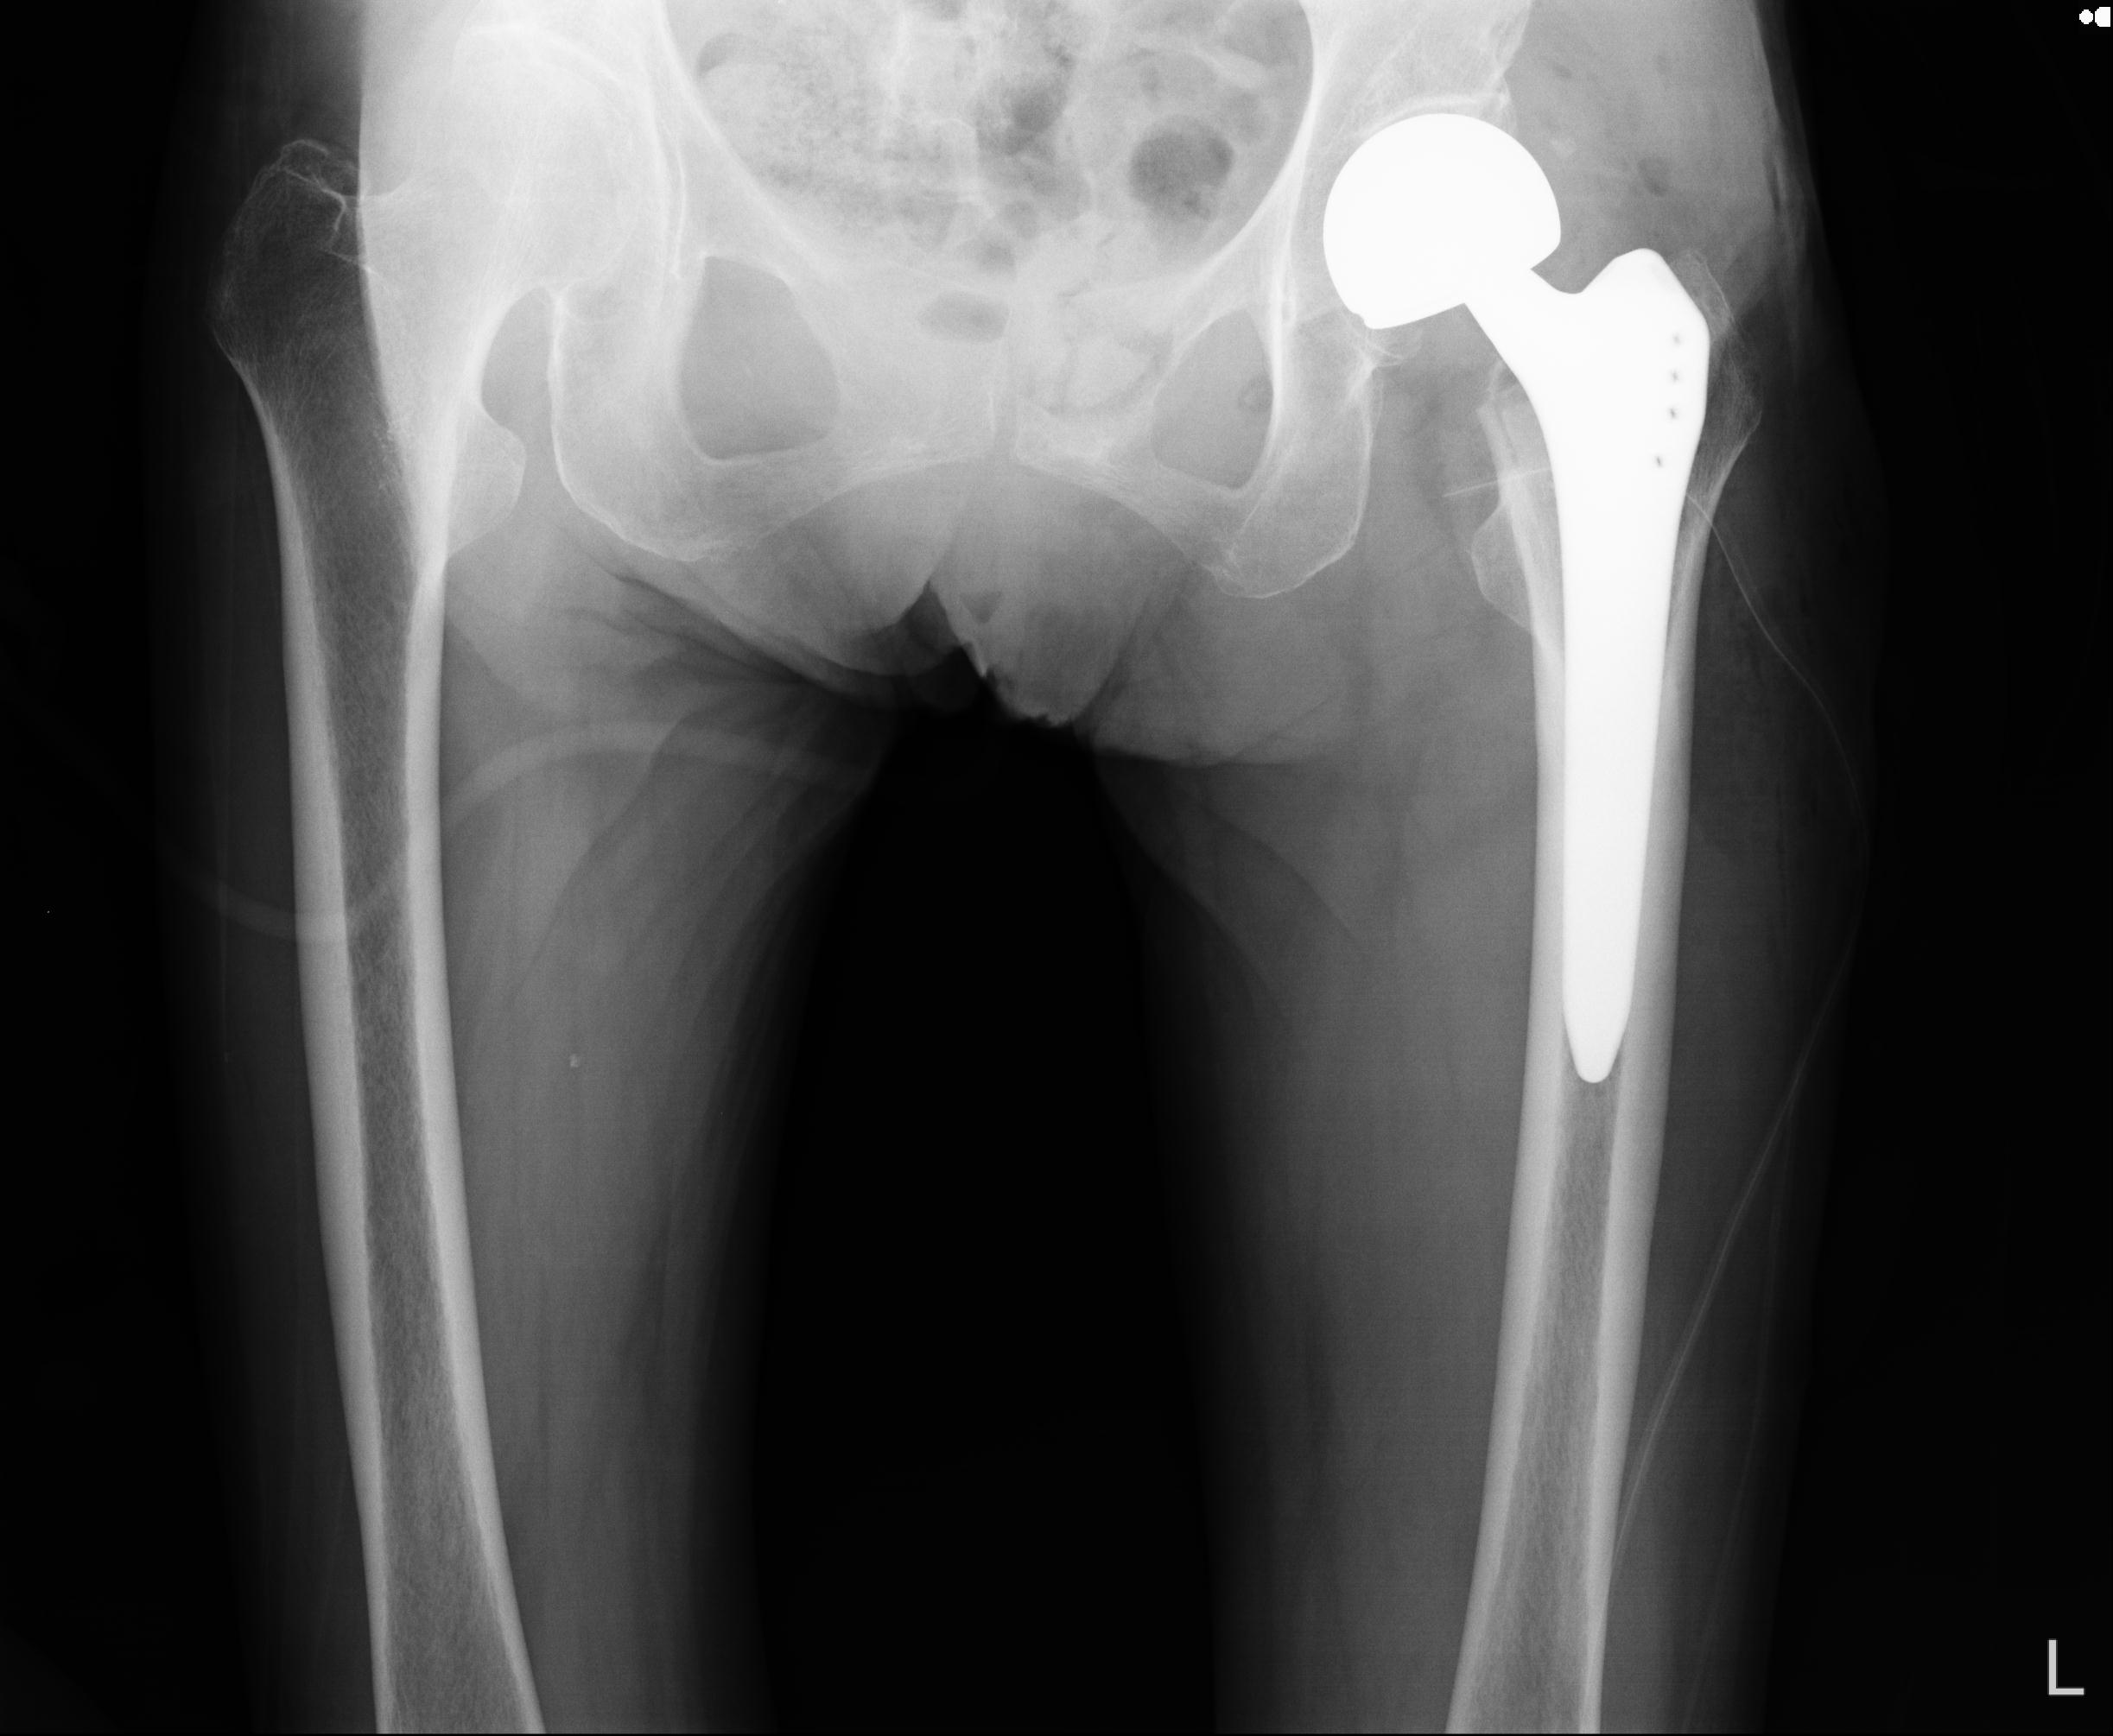

91569 3/25 両股正面とラウエン 70歳女性 人工骨頭+バンクーバー